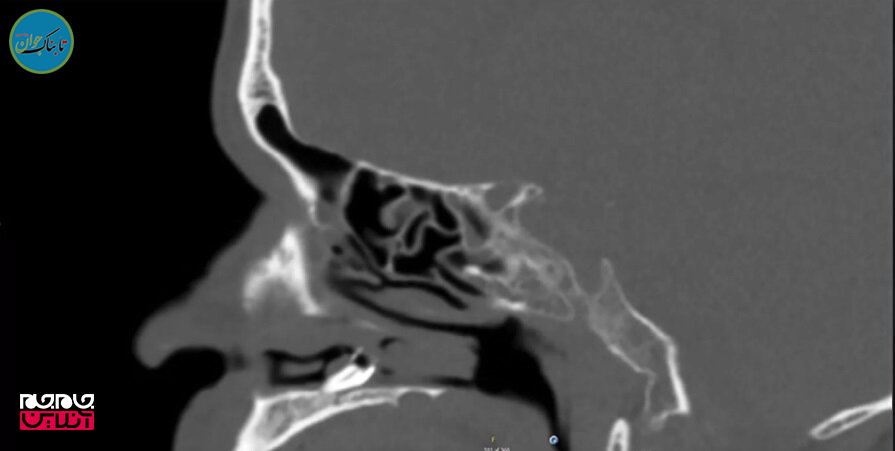

قبل از این تشخیص پزشکی عجیب مرد ۵۹ ساله روشهای مختلفی را برای درمان گرفتگی مجرای بینی خود آزمایش کرد و پس از آنکه نتیجهای نگرفت به بخش گوش و حلق و بینی بیمارستان دانشگاه Aarhus در دانمارک مراجعه کرد. در آنجا یک سی تی اسکن نشان داد تودهای در کف مجرای بینی او وجود دارد.

پزشکان این مرد ابتدا تصور میکردند این برجستگی یک کیست پوستی یا یک دندان باشد که در مکان معمول خود نروییده است.

بررسی بیشتر نشان داد این توده یک دندان است که با بافت متورم مجرای بینی پوشیده شده است.